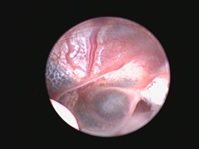

Риноскопия - это эндоскопическое исследование носовых ходов и носоглотки с помощью эндоскопа. Для исследования носовых ходов чаще всего используются жесткие эндоскопы, которые вводятся через ноздри в носовые ходы. Для осмотра носоглотки удобнее применять гибкие эндоскопы, осмотр проводится через ротовую полость. Сама процедура риноскопии проводится с активной санацией физиологическим раствором, что так же оказывает лечебный эффект, особенно при хронических и гнойных ринитах. Во время исследования осматриваются все носовые ходы ( вентральный, средний, дорсальный), а так же полость носоглотки, оценивается цвет слизистой, характер ее повреждений, оценивается проходимость и наличие инородных предметов, кист и новообразований. При обнаружении подозрительных участков слизистой, при хронических ринитах, новообразованиях- проводится взятие материла для гистологического исследования. Гистологическое исследование позволяет поставить более точный диагноз и исключить онкологическую природу заболевания.

Во время риноскопии помимо осмотра проводится и удаление полипов, кист и новообразований. Удаление образований выполняется с помощью специальных эндоскопических инструментов, очень важно, что удаление проводится под эндоскопическим контролем.

крупный полип носоглотки